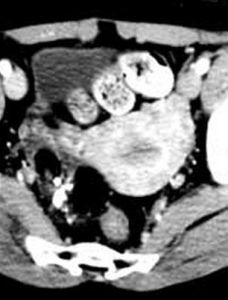

CT表現

1、典型的CT徵象為密度不均的囊性腫塊,單側或雙側性。

2、囊壁厚薄不均,邊緣光整。

3、內含脂肪密度影和發育不全的骨骼及牙齒,也可見自囊壁突起的實體性結節影。如囊內同時含有脂肪和液體,則可見到上脂肪下液體的液-脂界面,並可隨體位變動而改變位置。

4、如為皮樣囊腫時,CT僅表現為含液體的囊性占位,但囊壁可有蛋殼樣鈣化。

5、惡性畸胎瘤侵及鄰近組織,表現為腫瘤與周圍器官的脂肪層消失;腫瘤侵及膀胱、盆腔肌肉或腸管,則表現為與他們之間的分界不清。